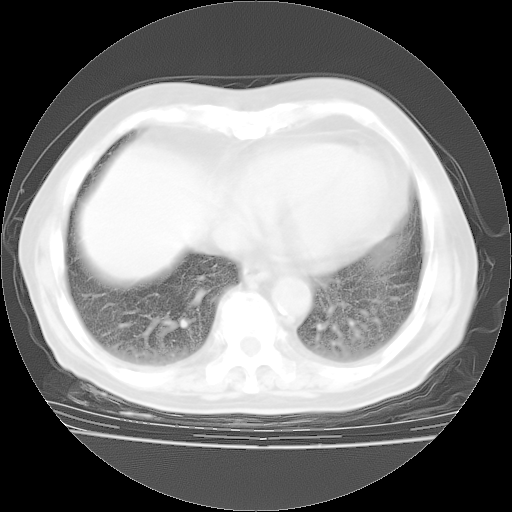

4月28日肺部CT——再次出现类似去年5月9日——磨玻璃样、间有“粟粒样”改变。